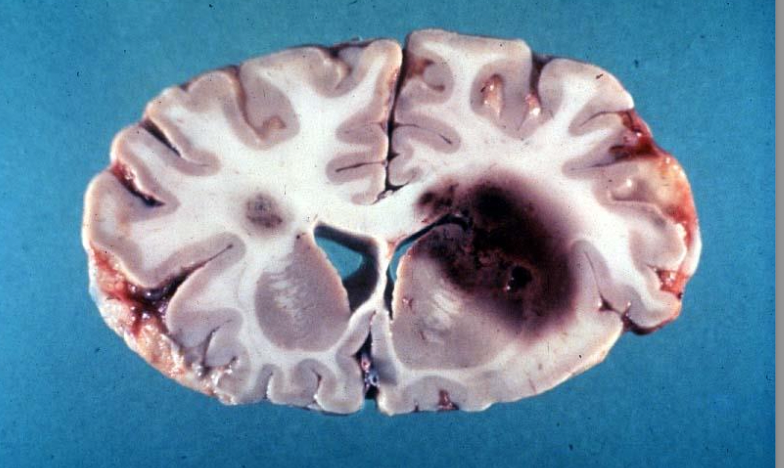

Glioblastoma

GBM with butterfly appearance